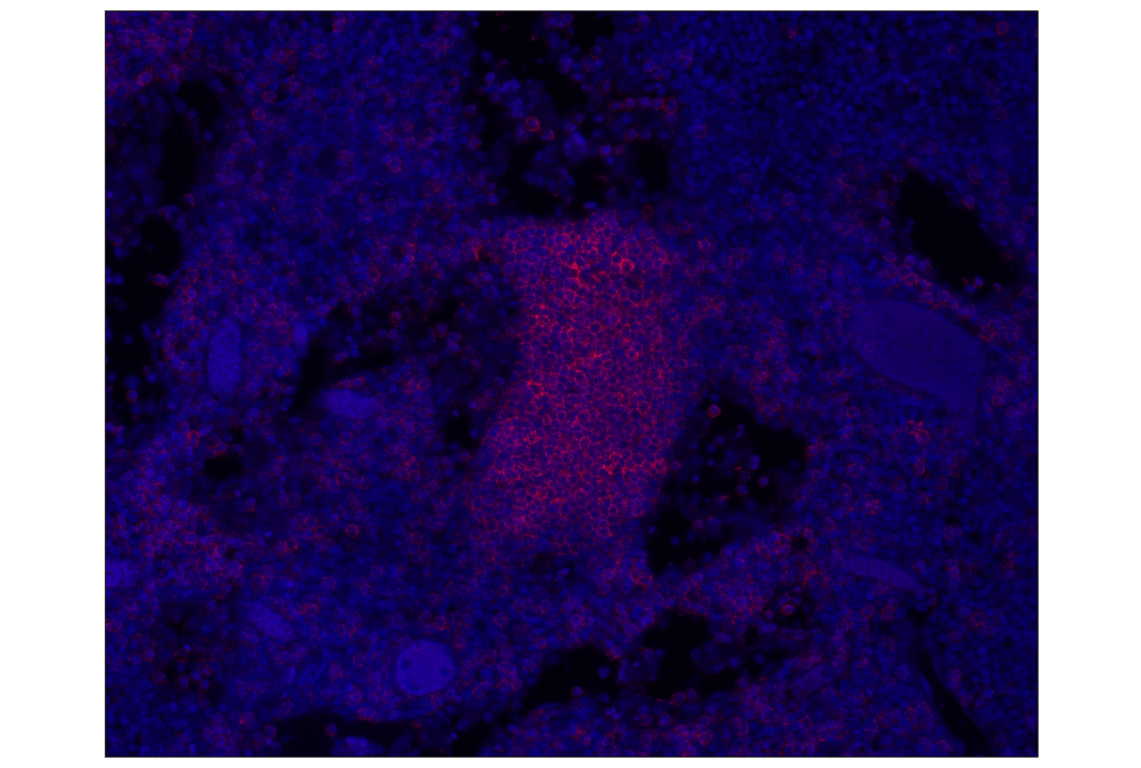

CD20 (E7B7T) Rabbit Monoclonal Antibody (Alexa Fluor® 555 Conjugate) #81546

Immunohistochemistry (Paraffin) 1:100 - 1:400

CD20 (E7B7T) Rabbit Monoclonal Antibody (Alexa Fluor® 555 Conjugate) recognizes endogenous levels of total CD20 protein.